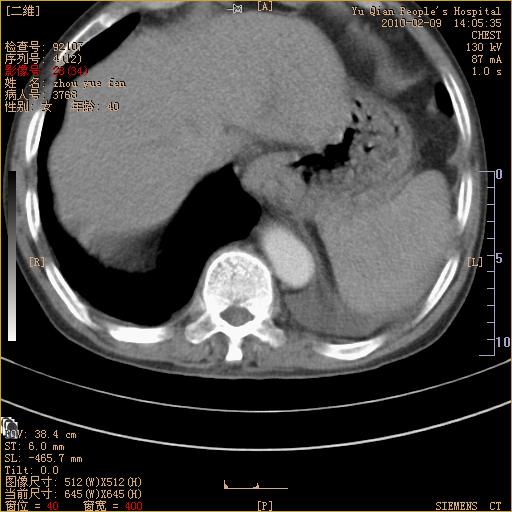

男性,73岁,咳嗽咳血数天,诊为肺ca伴左肺下叶后段阻塞性炎症、肺不张妥否?